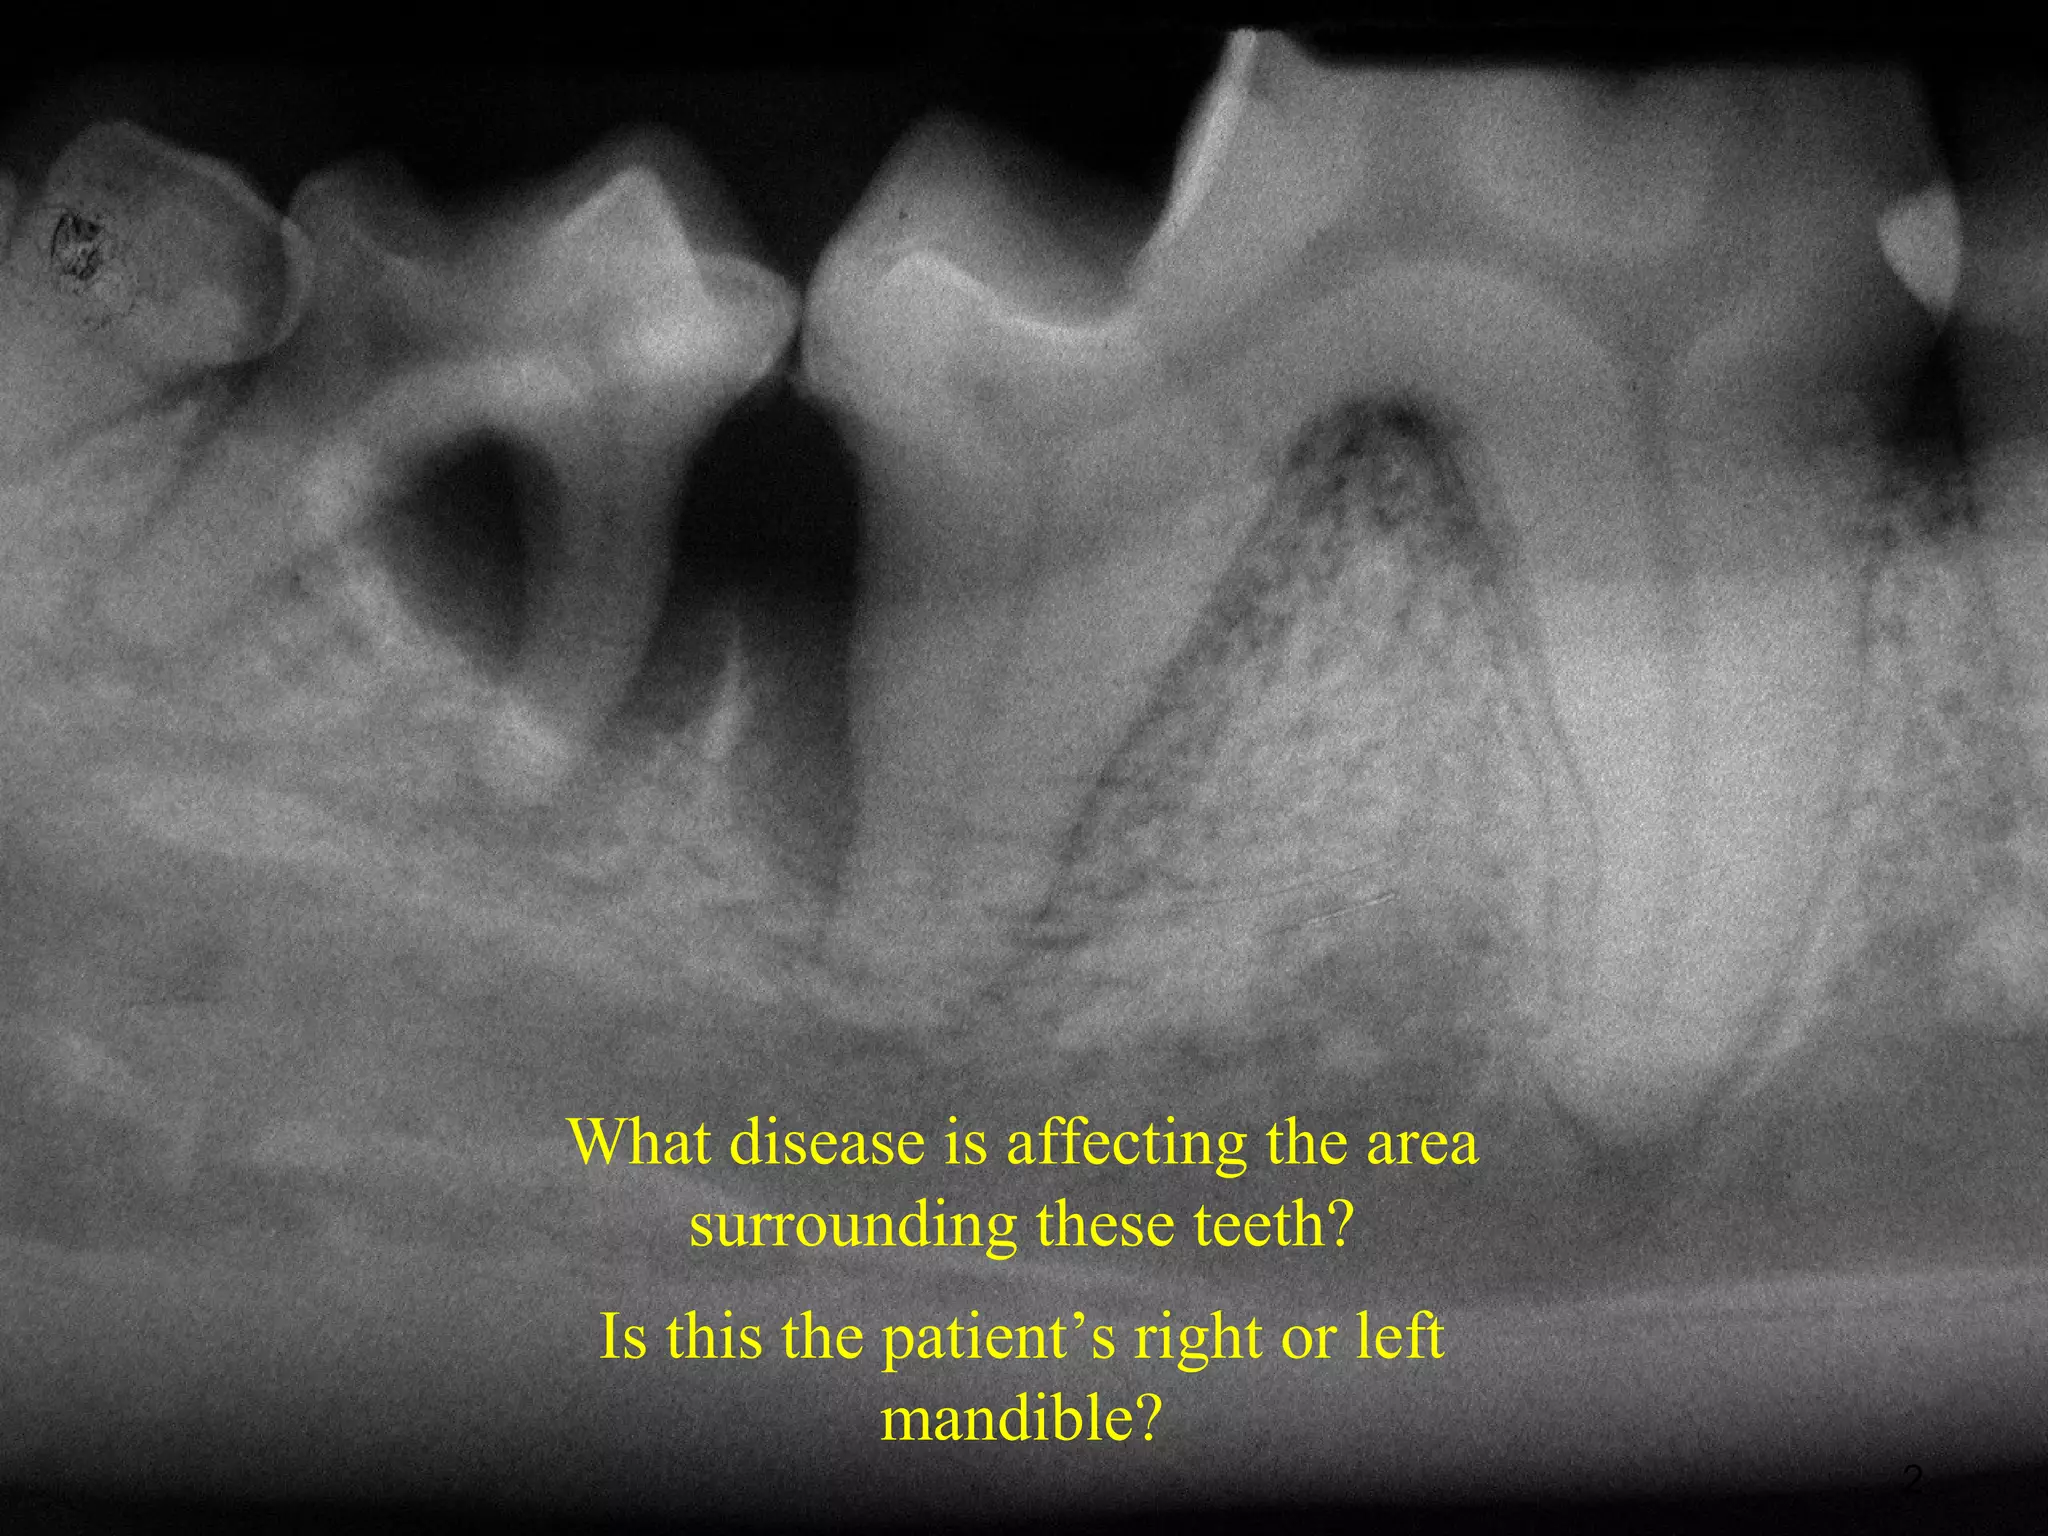

What disease is affecting the area

surrounding these teeth?

Is this the patient’s right or left

mandible?

2

What disease isaffecting the area surrounding these teeth? Is this the patient’s right or left mandible? 2